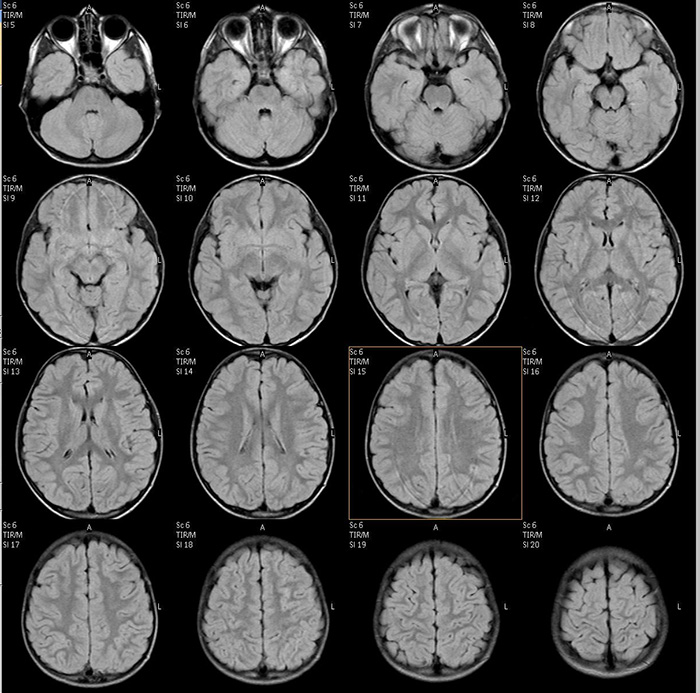

Рис. 3. МРТ данные пациента с ДЦП: на FLAIR изображениях структурные изменения минимальны.